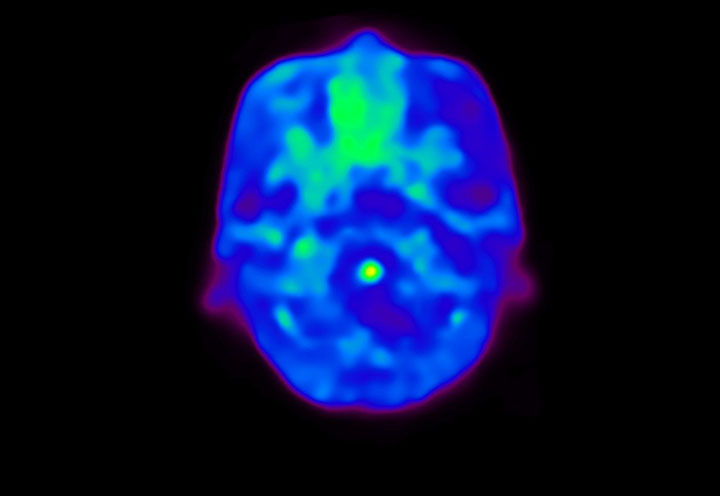

Head / Case4 : Amyloid

Coronal

Courtesy : Kindai University Hospital

- Imaging protocol

- Injected dose: 3.21 MBq/kg, 18F-Flutemetamol

- Uptake time: 100 minutes

- Scan time: 20 minutes